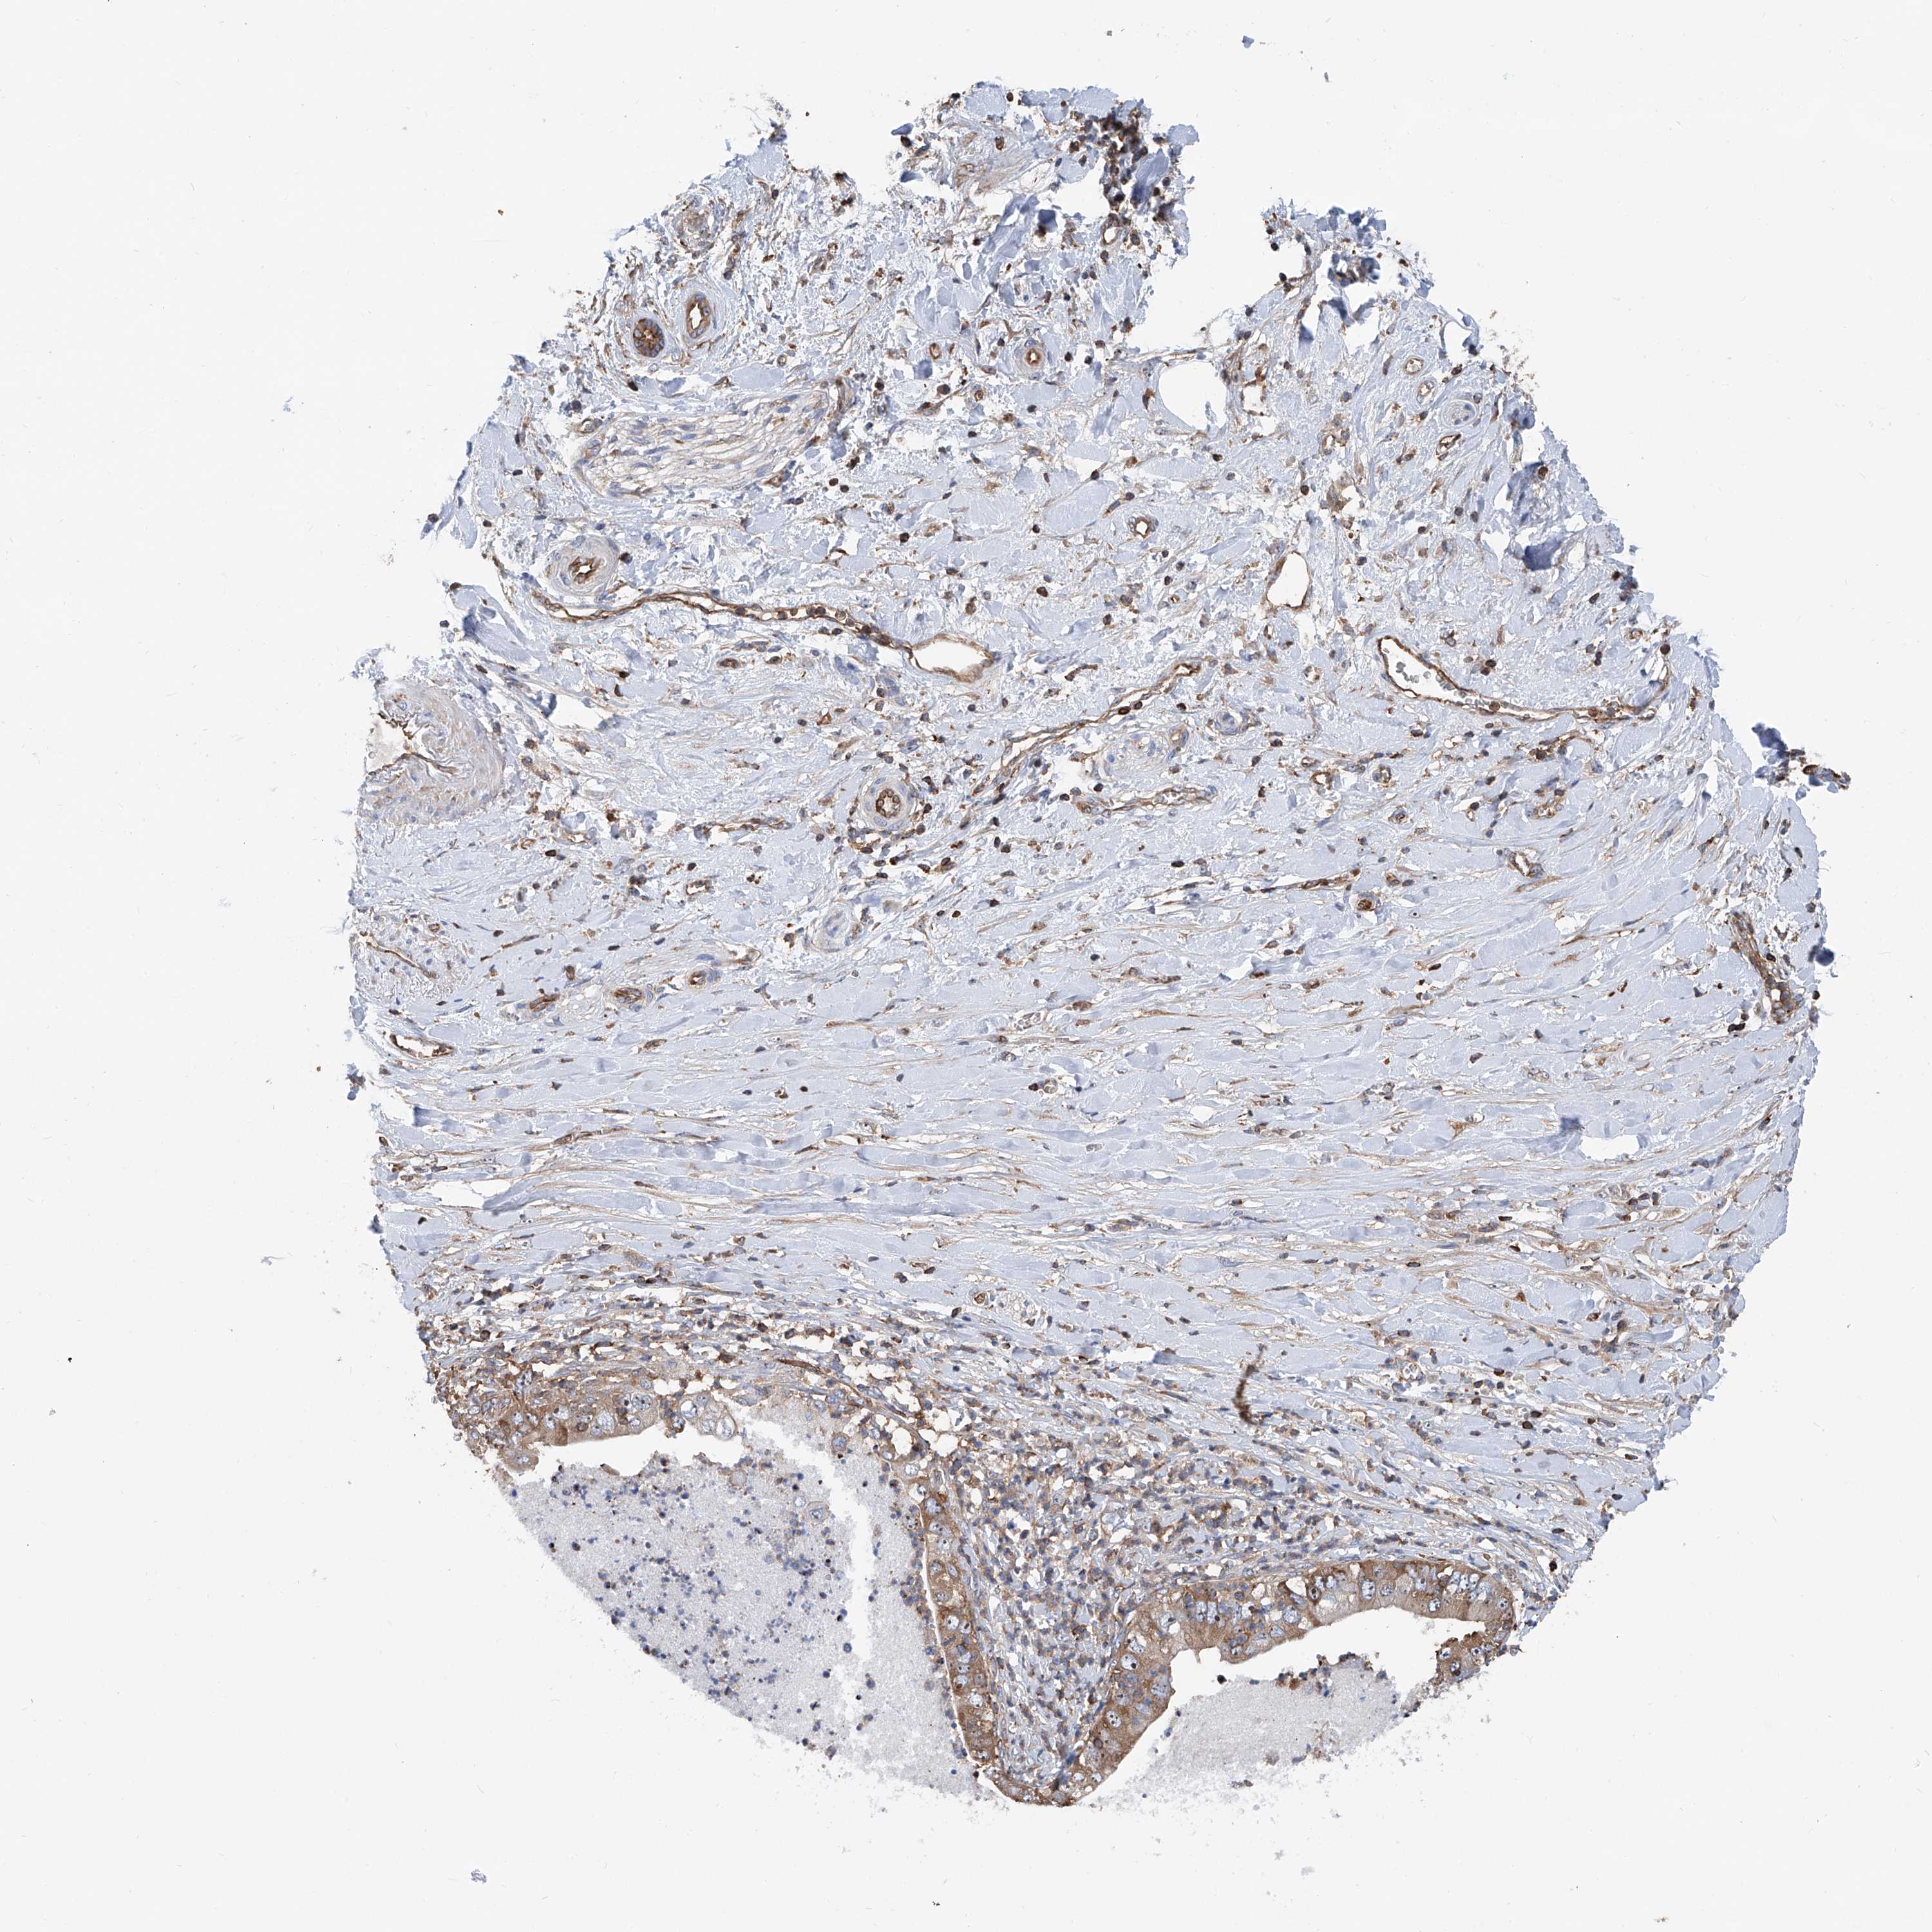

PANCREATIC CANCER - Protein expressioni

A mouse-over function shows sample information and annotation data. Click on an image to view it in a full screen mode. Samples can be filtered based on level of antibody staining by selecting one or several of the following categories: high, medium, low and not detected. The assay and annotation is described here.

Note that samples used for immunohistochemistry by the Human Protein Atlas do not correspond to samples in the TCGA dataset.

Antibody stainingi

Antibody staining in the annotated cell types in the current human tissue is reported as not detected, low, medium, or high, based on conventional immunohistochemistry profiling in selected tissues. This score is based on the combination of the staining intensity and fraction of stained cells.

Each image is clickable and will lead to virtual microscopy that enables deeper exploration of all samples and also displays staining intensity scores, fraction scores and subcellular localization as well as patient and tissue information for each sample.

Antibody HPA028973

Staining

High

Medium

Low

Not detected

Intensity

Strong

Moderate

Weak

Negative

Quantity

>75%

75%-25%

<25%

None

Location

Nuclear

Cytoplasmic/membranous

Cytoplasmic/membranous,nuclear

Adenocarcinoma, NOS